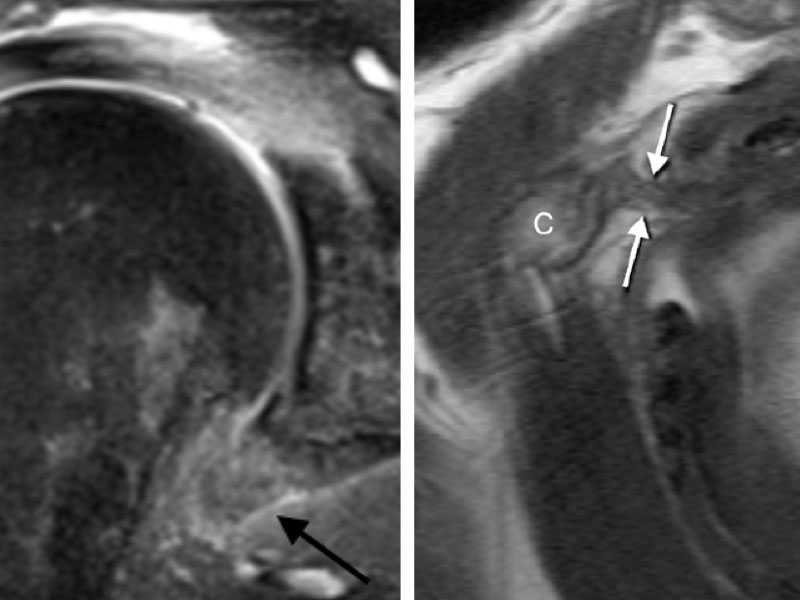

Imagem mostrando a capsula inflamada